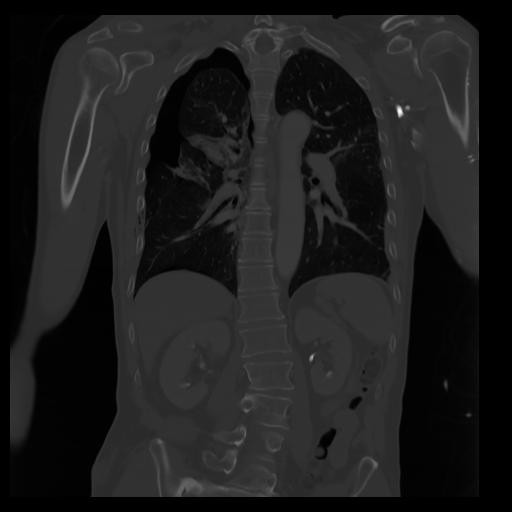

29 CUERPO,CE,Coronal,3.000,CUERPO,Coronal,